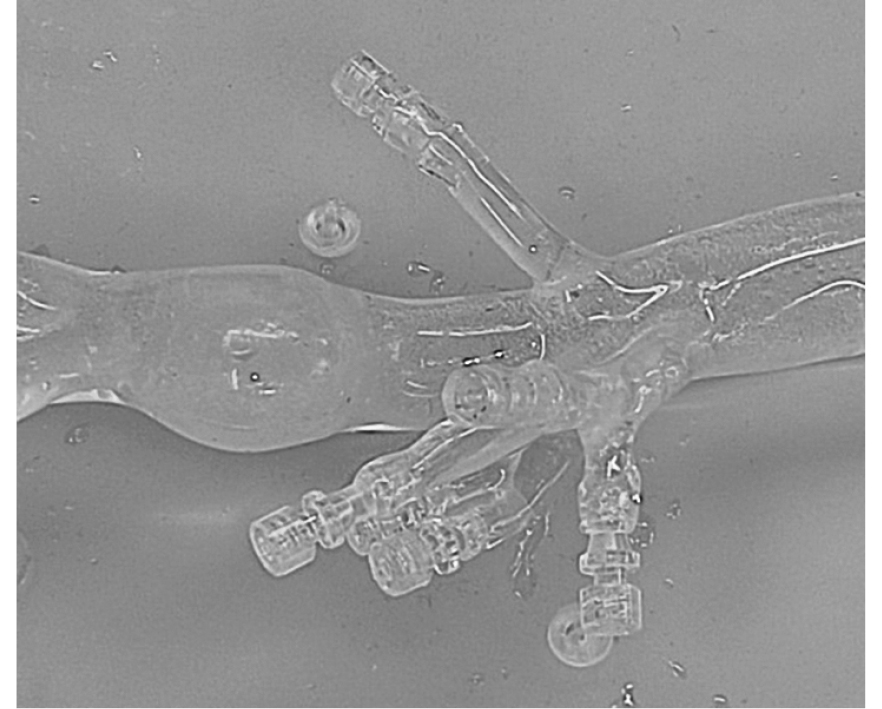

During the study, another issue that had to be resolved was the development of a frame base for branch modules for aortic branch prosthetics in the implantation zone of the main trunk (Fig. 2, a).

During design modeling and testing its experimental models on a bench, the optimal shape of the module was chosen, similar to a “nail” with a restrictive cap that prevents the branch stent from jumping out of the main trunk and not protruding into its lumen (Fig. 2, b). The intraoperative radiographs during the test implantations of the prototypes into a silicone phantom and biological objects of animals and necropsy materials obtained after their sacrifice confirmed the advantages of this sample.

In a trial assembly of stent-graft models from modules of various configurations, the cell size of the main module cannot be less than 1 cm; otherwise, strangulation of the branch module occurs with subsequent stenosis of its lumen at the base (Fig. 2, c). With a cell size corresponding to the diameter lateral outlet, stenosis does not occur (Fig. 2, d). In addition, an excessively rigid frame limits significantly the ability of the structure to adapt to the internal topography of the aorta. Thus, based on the results, the optimal stiffness and diameter of the nitinol wire from which the product frame was made were selected.

Fig. 2. Lead module: a — working drawing of the lateral branch: 1 — branch module; 2 — wall of the outgoing artery; 3 — frame mesh; 4 — shell of the stent graft; b — test samples of the lead modules; c — a prototype of the lateral branch, a cell of 5 mm; d — an experimental sample of lateral tap, cell 10 mm